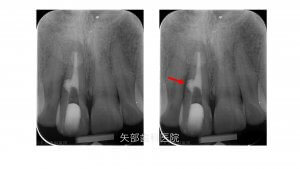

歯根内部吸収の治療

今回は内部吸収の位置と大きさををCBCTでイメージし根管内より不良肉芽の除去を電気メス等の器材で行いました。

しっかりと出血を止めることができたのでうまく充填することができました。

歯根中央部の内部吸収している穴はMTAセメントにて埋めています。

MTAセメントはその封鎖性と生体親和性で穿孔時の第一選択としています、今回も患者さんの同意が得られたので使用しています。